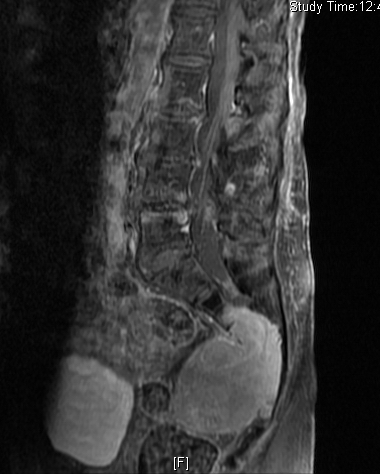

MRI (Fig. 4-10)

• Hyper enhancement with gadolinium (Fig. 6 & 7).

Fig. 4-10: MR image of a chordoma shows a destructive bone lesion in the sacrum that is hypointense on T1W images, hyperintense signal on T2W and enhancement of the lesion after gadolinium.